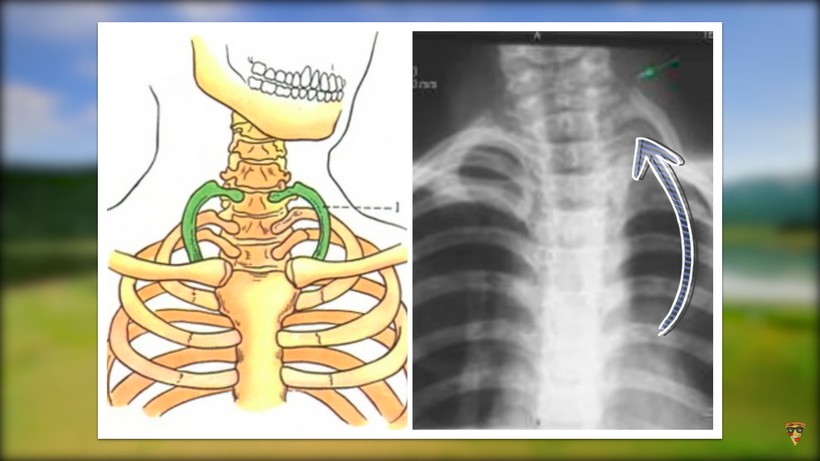

Дополнительные ребра. У обычного среднестатистического человека 12 пар ребер, но встречаются такие люди, кто имеет дополнительную пару. Эти два ребра растут из шейного позвонка. По статистике, всего один человек из 500 обладает такой особенностью. Но не факт, что ребра будут большими. В некоторых случаях они настолько малы, что человек не будет даже знать об их существовании. Однако есть и очень длинные дополнительные ребра. Они могут привести к ухудшению самочувствия из-за давления на кровеносные сосуды.